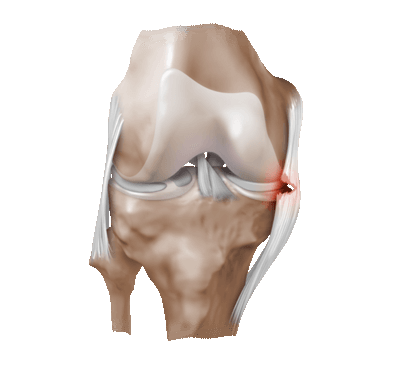

3. Кисты менисков нередко формируются на фоне горизонтальных или комплексных разрывов менисков. Если эти кисты проявляют себя клинически, может быть показана декомпрессия кисты, артроскопическая или открытая

4. Кисты чаще всего формируются при разрывах наружного мениска.